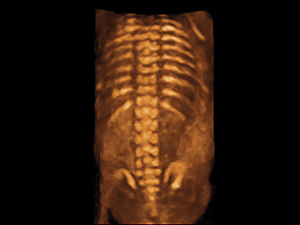

3D/4D Ultrasound

For a routine assessment of the fetal morphology, 2D ultrasound is already adequate. The addition of 3D and/ or 4D scan is a bonus and may enhance the bonding between the family and the unborn child. Most women also find it pleasurable watching the 3D/4D pictures of their babies. 3D/4D ultrasound is increasingly important when fetal abnormalities are suspected or picked up. These new modalities of ultrasound can help by clarifying the abnormalities. The 3D ultrasound pictures may also help the family appreciate to what extent the baby is affected.

3D fetal spine at 20 weeks